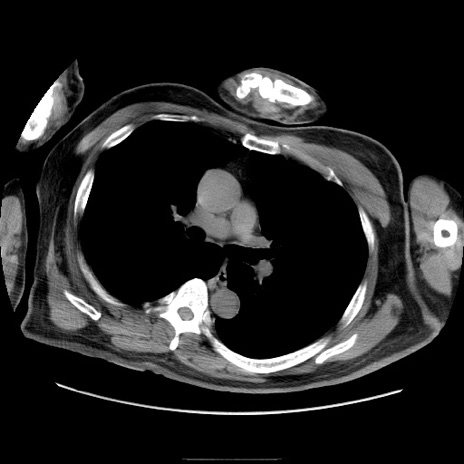

症例22(横断像)

【症例】50歳代男性

【主訴】腹痛

【現病歴】AVMからの被殻出血のため回復期リハ病棟入院中。 本日午後3時頃急に下腹部痛が出現した。

【既往歴】AVM、被殻出血、虫垂炎、高血圧

【身体所見】意識晴明、左半身不全麻痺、会話の理解は良好、36.5°C、腹部:膨隆、全体に板状硬、下腹部正中に圧痛点あり、反跳痛-、筋性防御不明、右下腹部にope scar

【データ】WBC 9400、CRP 0.06